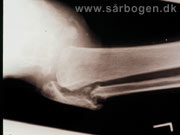

Charcot i ankel (rtg...

Zoom